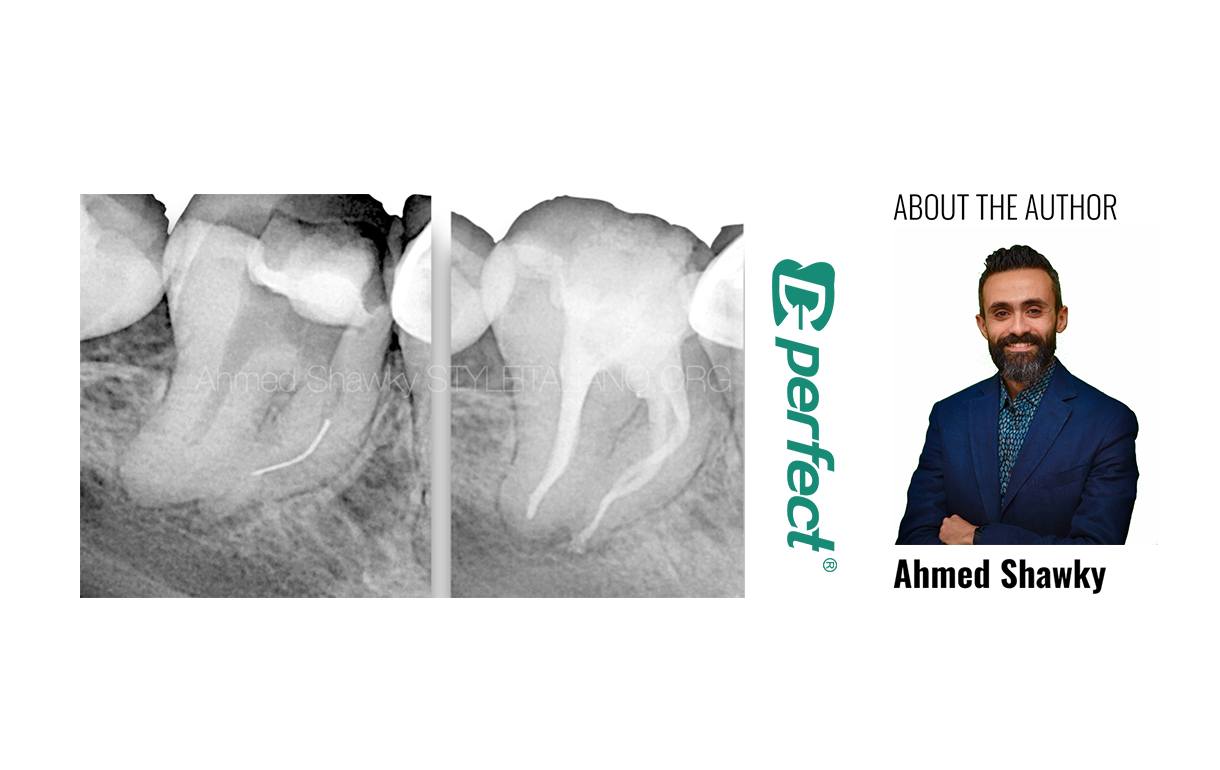

Pretreatment evaluation involved clinical and radiographic examination, which confirmed a symptomatic apical periodontitis in the mandibular right second molar.

2D and CBCT evaluation revealed a small hand file separated in the ML canal, CBCT was mandatory to plan the retrieval approaching relevance to the respective anatomy.

The configuration of the mesial root canal system was shown to have multi-planar curvatures, highlighting the reason for file separation

The instrument probably separated due to the improper shaping strategy followed for shaping of the double curved mesial root canals.